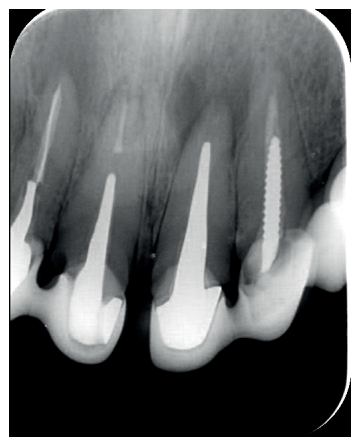

El paciente aporta como estudio radiológico una ortopantomografía (OPG), (Figura 1). Se realizaron radiografías periapicales (Figuras 2 y 3), así como exploración clínica incluyendo la valoración periodontal de los dientes afectados, sin observar profundidades de sondaje aumentadas que pudieran indicar la existencia de lesiones endoperiodontales.

A los seis meses el paciente acudió a revisión sin ninguna sintomatología, tanto a nivel anterior como posterior. En las radiografías periapicales se apreció una disminución en el tamaño de las lesiones periapicales radiolúcidas preexistentes (Figuras 10 y 11). Dado que faltaba tratar la lesión del 25, se realizó CBCT de control donde se comprobó la mejoría a nivel del 26 (Figura 12), por lo que se programó la microcirugía del 25.

Para el correcto diagnóstico de lesiones radiolúcidas a nivel periapical es importante disponer de imágenes radiológicas que muestren con precisión la situación y tamaño de dichas lesiones. En nuestro caso el paciente aportaba una ortopantomografía. Este tipo de radiografía no es adecuada para el diagnóstico en endodoncia. La radiografía periapical aporta mejor definición, especialmente a nivel anterior, ya que presenta una menor distorsión. Actualmente el CBCT es la prueba radiológica más fiable, ya que proporciona imágenes en las tres dimensiones del espacio, lo que permite diagnósticos más precisos1,2 .